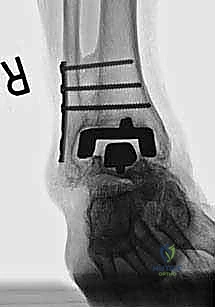

مراجعة مفصل الكاحل الصناعي هي إجراء جراحي ضروري لمعالجة المشاكل التي قد تنشأ بعد الجراحة الأولية، مثل كسور الكعبين أو عدم استقرار المفصل. يتضمن العلاج التشخيص الدقيق عبر الأشعة السينية والتصوير المقطعي، يليه التدخل الجراحي لتثبيت الكسور واستعادة وظيفة الكاحل، مع التركيز على التعافي المبكر.

تُعد جراحة مراجعة مفصل الكاحل الصناعي (Revision Total Ankle Replacement) من الإجراءات الجراحية المتقدمة والبالغة الدقة في عالم جراحة العظام الحديثة. لا تقتصر هذه الجراحة على مجرد استبدال مفصل تالف بآخر جديد، بل هي عملية إنقاذ معقدة للغاية تهدف إلى معالجة المشاكل الميكانيكية والبيولوجية التي تنشأ بعد الجراحة الأولية. من أبرز هذه المشاكل: الفشل الميكانيكي للمفصل، تحلل العظام (Osteolysis)، أو حدوث كسور معقدة في الكعبين (Malleolar Fractures) المحيطة بالمفصل الصناعي. يتطلب هذا الإجراء تقييماً سريرياً وشعاعياً دقيقاً يشمل التصوير المقطعي ثلاثي الأبعاد والأشعة السينية، يليه تدخل جراحي دقيق لاستعادة التوازن الحيوي والميكانيكي للكاحل والحفاظ على الطرف من البتر أو الدمج.

إن نظام (Agility) لمفصل الكاحل كان يُعد في وقت من الأوقات ثورة في عالم جراحة العظام، حيث اعتمد تصميمه على دمج المفصل الليفي الظنبوبي الشظوي (Syndesmosis) لتوفير قاعدة عريضة وثابتة للمفصل الصناعي. ومع ذلك، بمرور السنوات، أظهرت الدراسات والمتابعات السريرية أن بعض المرضى يعانون من مضاعفات مثل عدم التئام هذا الدمج، أو هبوط المفصل (Subsidence)، أو تكون أكياس عظمية تؤدي إلى تخلخل الزرعة.

- الأشعة السينية مع تحميل الوزن (Weight-bearing X-rays): لتقييم الزوايا الميكانيكية وتحديد مدى هبوط المفصل أو وجود كسور في الكعب.

كسور الكعبين (Malleolar Fractures) المصاحبة للمفصل الصناعي

من أعقد التحديات التي تواجه جراحي العظام هي حدوث كسور في الكعب الداخلي (Medial Malleolus) أو الخارجي (Lateral Malleolus) في وجود مفصل صناعي. تحدث هذه الكسور لعدة أسباب:

1. ترقق العظام: حول المفصل الصناعي نتيجة لعدم استخدام الطرف بشكل طبيعي (Stress Shielding).

2. الاصطدام الميكانيكي (Impingement): إذا كان حجم المفصل الصناعي أكبر من اللازم، فقد يضغط على الكعبين من الداخل ويؤدي لكسرهما بمرور الوقت.

3. الإصابات المباشرة: مثل السقوط أو التواء الكاحل.

علاج هذه الكسور يتطلب مهارة فائقة من الدكتور محمد هطيف، حيث يتم استخدام تقنيات الجراحة الميكروسكوبية وتثبيت الكسور باستخدام صفائح معدنية دقيقة ومسامير (Locking Plates) دون المساس بثبات المفصل الصناعي، أو يتم دمج علاج الكسر ضمن عملية مراجعة المفصل الكلية إذا كان المفصل نفسه تالفاً.

يتم إدخال المفصل الجديد المخصص للمراجعة، والذي يحتوي غالباً على سيقان (Stems) تدخل عميقاً في عظمة الساق وعظمة الكاحل لضمان الثبات الميكانيكي. في حال وجود كسور في الكعب، يتم تثبيتها في هذه المرحلة.